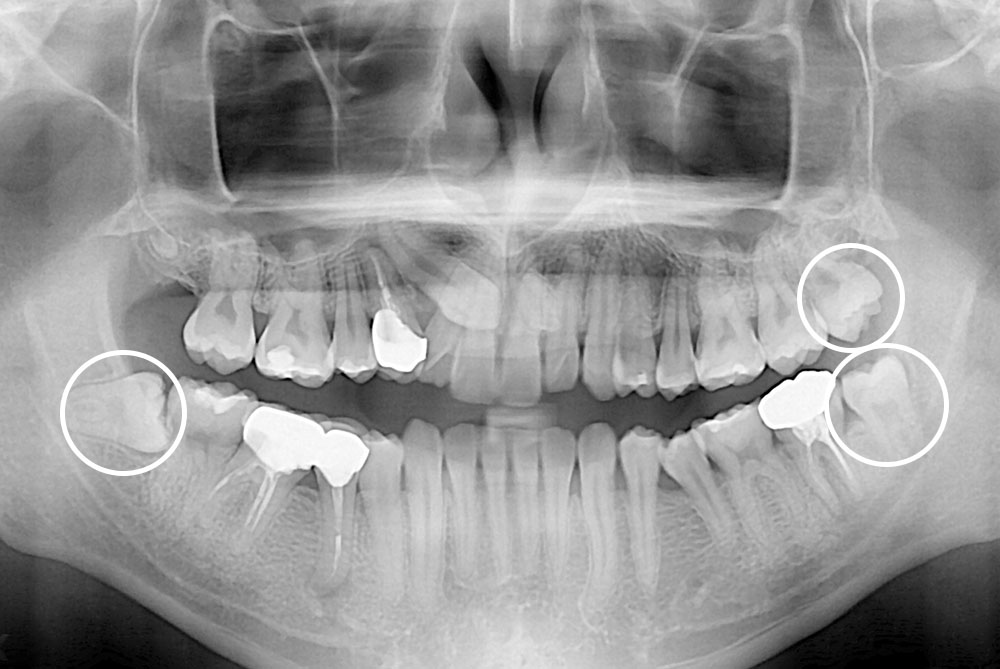

[사랑니] 매복 사랑니 발치

치료후 : 2018-12-14

세종치과는 구강악안면외과학 박사이신 원장님이 발치하는 치과입니다